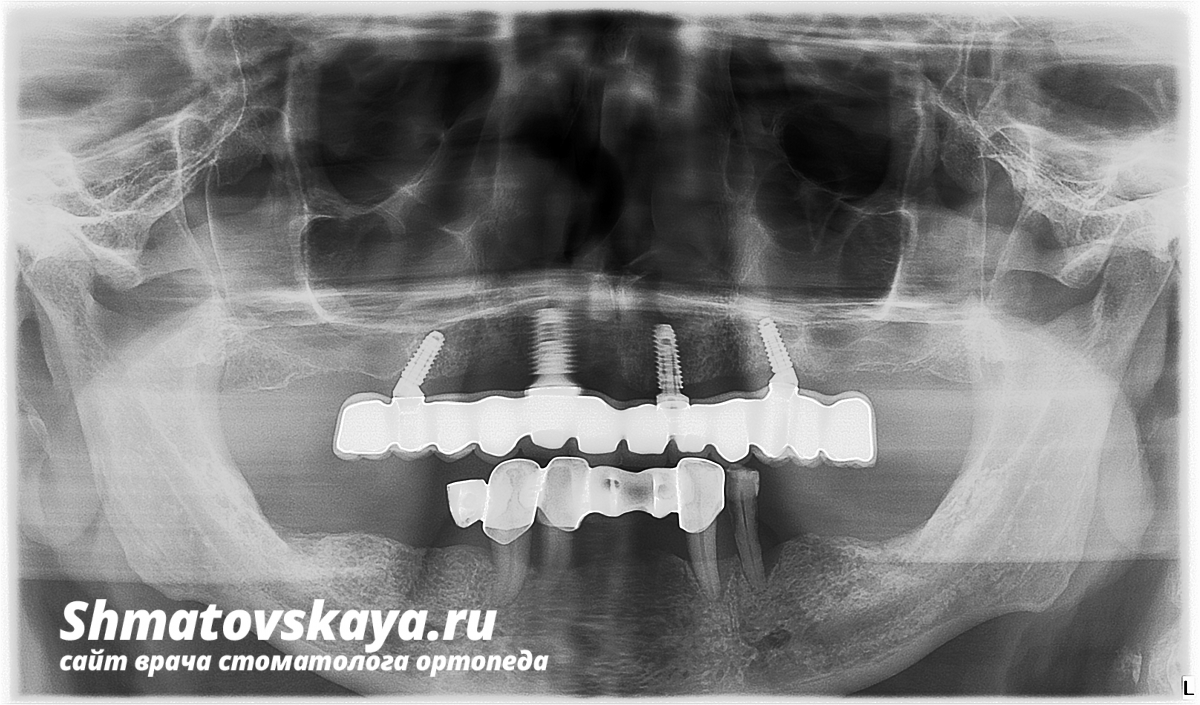

Металлокерамическая конструкция на балке на 4-ёх имплантатах (Osstem) верхняя челюсть

ОПТГ

1. Проведено 3-D исследование (КЛКТ);

2. Установлены имплантаты на в/ч;

3. Через 4 месяца установлены абатменты  Multi;

4. 3-D моделирование верхней челюсти;

5. В течение 3-ёх недель изготовлена постоянная ортопедическая конструкция;